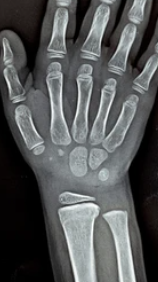

1. X선 검사 (X-ray): 일반적으로 성장판을 검사하는 방법으로 손목의 X선 사진을 찍어 성장판의 상태를 평가하는 방법입니다. 손목 관절 부위의 성장판이 어떻게 닫혔는지 확인하여 성장 가능성을 판단할 수 있습니다.